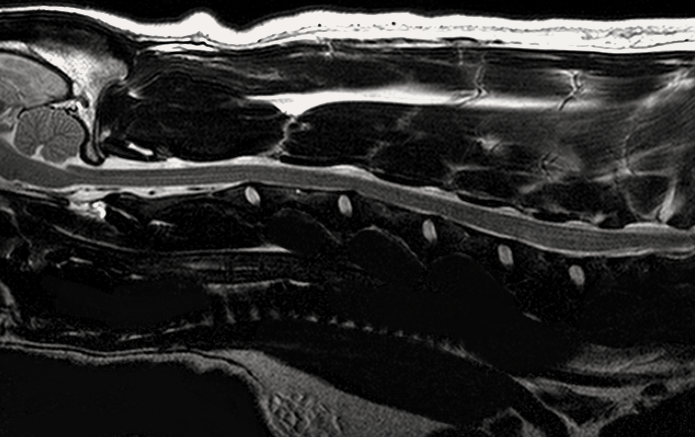

МРТ исследования проводятся на аппарате высокого качества Phillips Intera с напряженностью магнитного поля 1,5 Тесла. Позволяет максимально точно визуализировать анатомические структуры одинаково хорошо животному от 200г до 200кг

- Проведение мрт животному

- При нарушении походки или координации движения,

- Подозрении на повреждения/ заболевания головного или спинного мозга,